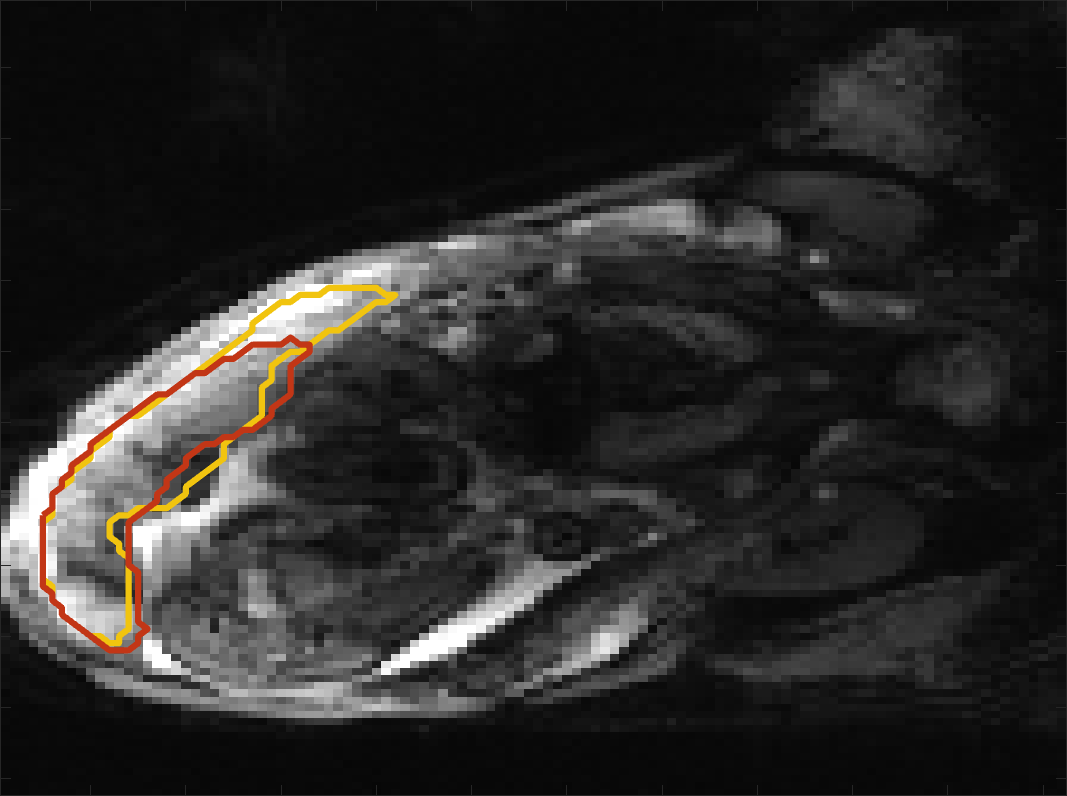

Figure 4 compares the predicted label maps with ground truth on subjects with increasing Dice scores using the BW-CE model. The model accurately identifies the location of the placenta, but in the worst cases misses boundary details.